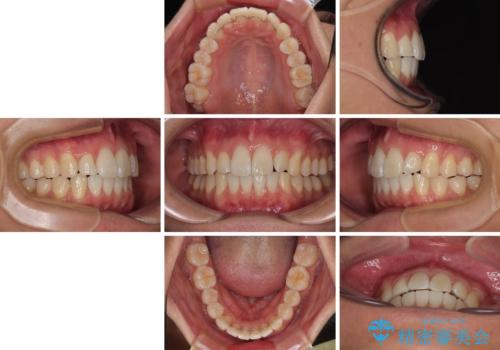

前歯のデコボコをインビザラインで綺麗に改善

- 上下前歯のデコボコとクロスバイトを気にして来院された患者様です。

インビザラインを用い、IPR(歯と歯の間を削る)と歯列全体を拡大させることで、歯並びを整えていくこととしました。

毎日22時間の装着時間を徹底してくださったのですが、左右ともに臼歯が咬合しなくなるという、インビザライン独特の症状が強く長く続いてしまい、終了するまでに長期間を要してしまいました。